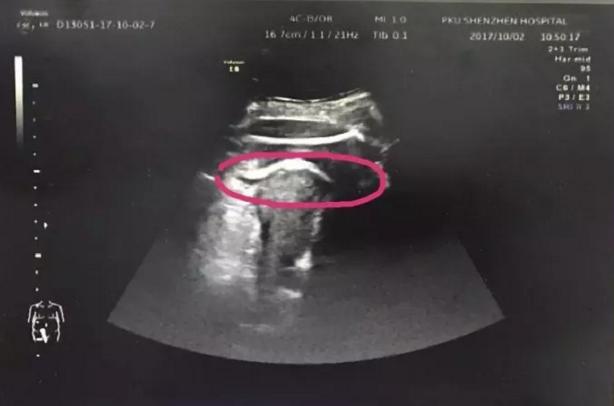

在B超室,医生检查发现孕妇 腹腔大量积液 ,而且在宫前壁近宫底处,胎儿股骨回声在子宫肌层以外,患者该处触痛也非常明显,肝肾间隙积液明显。

“虽然没有找到子宫的破裂口,但通过B超可以看到,在孕妇腹部最疼的地方,先看到的是孕妇的皮下脂肪,然后看到的是胎儿的腿,最后才看到孕妇子宫。胎儿的腿已经‘冲破’了子宫进入腹腔,大腿根正卡在子宫壁上。”北大深圳医院超声影像科石宇博士告诉记者。